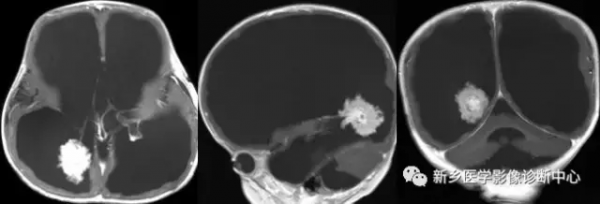

邊界清楚的圓形或類圓形等-高密度腫塊,密度均勻或不均勻,常伴有不同程度的鈣化或出血。增強可有輕度到中度增強,強化程度與病灶內血栓形成和鈣化有關,典型表現為不均勻的斑點狀增強。

病灶周圍一般無水腫,無或僅輕度佔位效應。MRI呈邊界清楚的混雜訊號,周圍有完整的低訊號含鐵血黃素環,病灶呈“爆米花”狀,具有特徵性。

病灶內含有不同階段的出血是訊號不均勻的原因;T1WI呈高訊號,是海綿狀血管瘤的特徵。增強可明顯強化,也可強化不明顯。